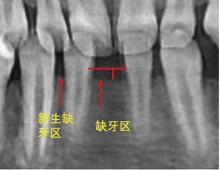

曲幸辉. 下颌先天性缺失一颗恒切牙的正畸学研究[J]. 医学综述, 2014, 20(22): 4099-4101.

Al-Ani AH, Antoun JS, Thomson WM, et al. Hypodontia: An update on its etiology, classification, and clinical management[J]. Biomed Res Int, 2017, 2017: 9378325.

庞光明, 周宏原. 下颌切牙先天缺失错牙合畸形的临床矫治[J]. 临床口腔医学杂志, 2004, 20(9): 563-564.

冯海兰. 先天性缺牙的口腔修复治疗Ⅱ先天性缺牙的临床表现[J]. 中华口腔医学杂志, 2011, 46(3): 188-189.

陈远萍, 宋继超, 胡敏. 伴有先天缺牙的错牙合畸形的矫正治疗[J]. 口腔正畸学, 2004, 11(3): 110-112.